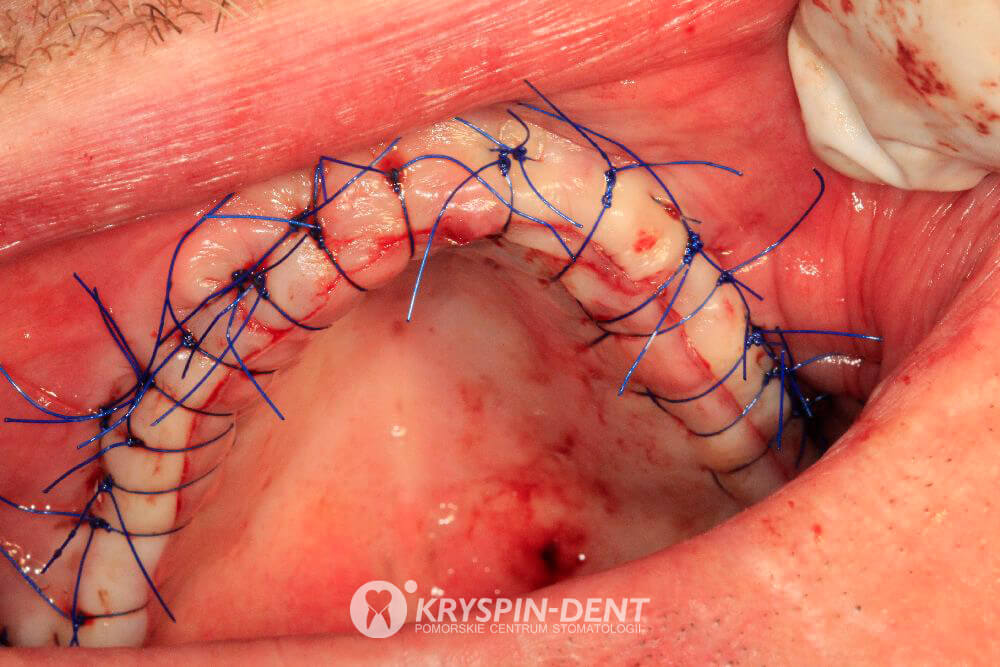

- Dzięki zaawansowanym zabiegom chirurgicznym odtworzono brakującą kość i uzyskano miejsce na wszczepy implantów.

- Wykonano wszczepy 4 implantów na górze oraz 4 implantów na dole stanowiące podstawę pod stałą (nie wyjmowaną) pracę protetyczną.

Bezpośrednio po wykonaniu protez przeprowadzono zabiegi z zakresu przeszczepu i regeneracji kości / odtworzenia kości w celu przygotowania miejsca dla przyszłych implantów